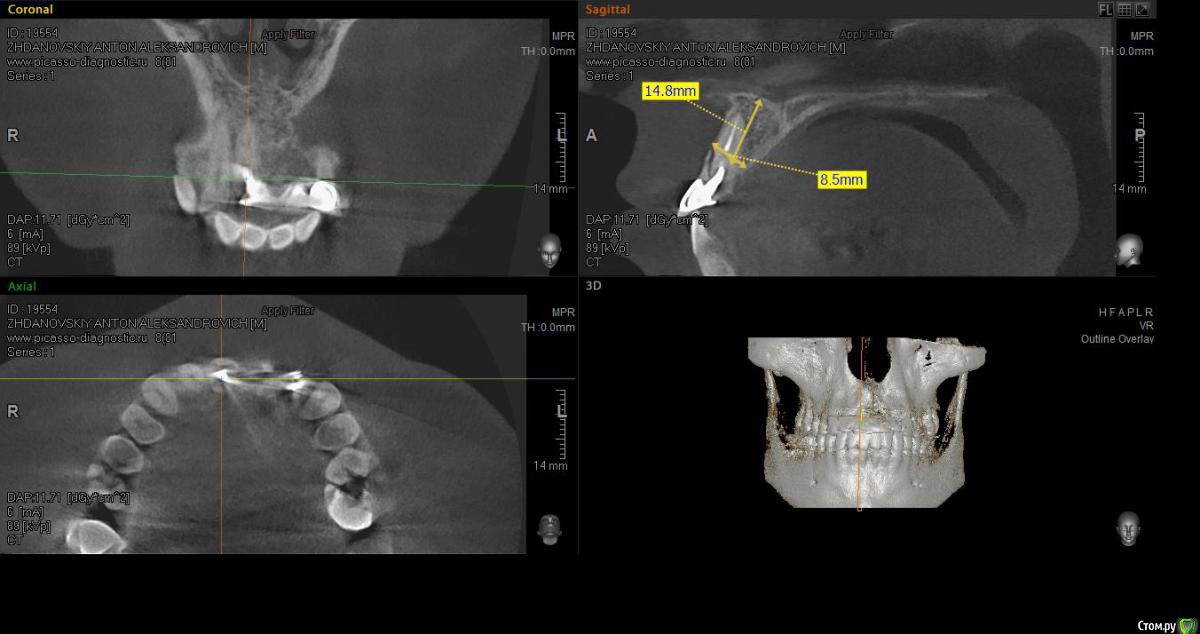

elen_only Опубликовано 1 августа, 2018 Поделиться Опубликовано 1 августа, 2018 Здравствуйте,коллеги! Помогите ,пожалуйста,неопытному имплантологу спланировать операцию. Пациент направлен ортопедом на удаление 11,22 зубов по поводу трещин корней. Биотип десны тонкий. Похоже,оставлен артефакт в области 21. Опыта одномоментной имплантации ,к сожалению, нет. Нервничаю.Хочу атравматично удалить 11,22 ,установить имплантаты с заглушками. Пациенту готовят сьемное на время. Через 4 месяца,поработать с десной. А корень попробовать достать через микроразрез,не отслаиваясь широко,такой опыт уже был. Подскажите,правильно ли я спланировала операцию? Или лучше сначала удалить корень а потом удалять зубы и имплантировать? Ссылка на комментарий

Bier Опубликовано 1 августа, 2018 Поделиться Опубликовано 1 августа, 2018 К сожалению,опытных хирургов-имплантологов рядом нет. У самой есть опыт двухэтапников,20+. Почему нельзя заглушку?.а если не будет первичной стабильности?, Планировали сьемную капу,не касающуюся деснычестно скажу, 20+ совершенно недостаточно для имплантации фронтального отдела. У вас по классификации ITI экстра сложный кейс. Что тут надо делать:1. атравматичное удаление, 2. Установка имплантатов с приданием нёбного положения (параметры эстетического окна) с достаточным торком (не менее 20-25) и правильным заглублением 3. Графт лунок 4. Подсадка ССТ (обязательно!!!!) 5. В зависимости от торка установка формирователей десны (желательно индивидуальных) или временных коронок.Если будут ФДМ , то каппа с зубами - правильный вариант временной конструкции. Так бы и называли, чтобы не вызывать вопросов. 3 Ссылка на комментарий

колесников Опубликовано 2 августа, 2018 Поделиться Опубликовано 2 августа, 2018 Свои 5 копеек вставлю. С одной стороны одномоментный малоинвазивная имплантация во фронтальной зоне с прогнозируемым эстетическим результатом -высший пилотаж и даже мелкая неудача, на поздних сроках, тяжело поддаётся корректировке,это надо понимать. Но с другой стороны,надо же когда то начинать.Касаемо вашего случая. 22 однозначно удалится с вестибулярной компактной пластинкой,вы должны иметь в запасе несколько вариантов закрытия этой проблемы с долгосрочным прогнозом. На мой взгляд более значительная проблема в зоне 21,после удаления 22 вероятно ткани подтянуться и сосочек 21-22 будет утрачен ,даже если вы сразу добавите объём в обл 21 и по началу будет казаться что все красиво получилось. Рекомендовал бы для атравматичноного удаления 22го ортодонтическую экструзию на неделю -самый простой вариант для вас . Сам бы наверно удалял с выделением щита. Еще вариант IDR. Другие способы считаю очень рискованными. И однозначно немедленная нагрузка. 3 1 Ссылка на комментарий